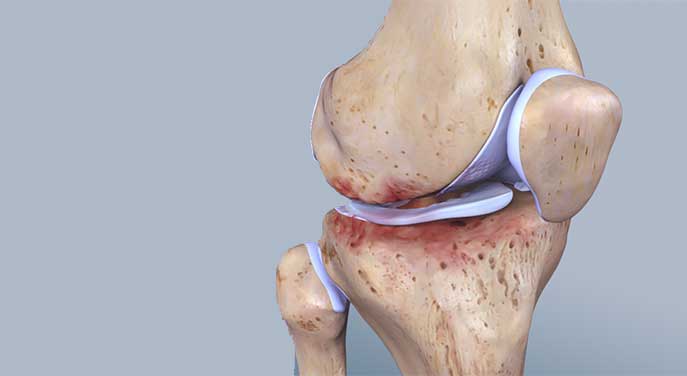

The meniscus is a kind of cartilage in the knee that acts as a load distributor for the body’s full weight. At one time, it was thought to be like the appendix: you wouldn’t miss it if it were gone. But now, it’s known that just a small tear in the meniscus – usually caused by a sports injury – increases the risk of osteoarthritis later in life, even if the damaged tissue has been removed.

On the other hand, lack of use can also lead to deconditioning of the meniscus and increase arthritis risk. You’ll notice the short-term effect of deconditioning when you get out of bed in the morning and feel stiff, but then your joints loosen up once you’ve moved around for a while. The same thing happens to astronauts in space unless they use specially designed resistance equipment to make up for the lack of weight-bearing exercise in microgravity.

Adesida’s team has developed bioengineered meniscus tissue grown from cells that have been removed from the damaged menisci of otherwise healthy individuals. The hope is one day to replace damaged tissue through transplant, preventing the development of knee osteoarthritis.